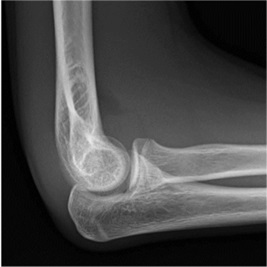

Example X-rays

|

A posterior fat pad is always abnormal |